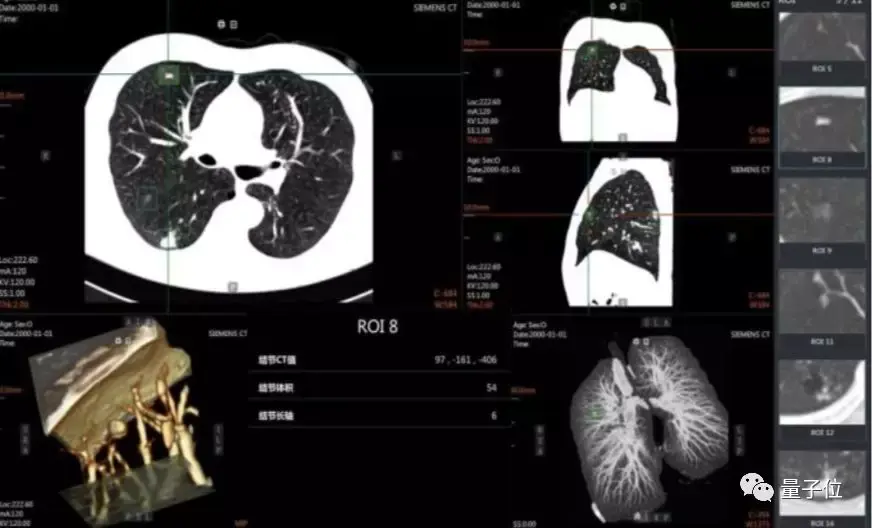

绝技二:AI+云,部署更强医疗影像分析应用

伴随着医疗体系现代化建设,医疗设备也已逐渐普及,即便在基层医疗机构,患者也能进行各类医学影像检查。

虽然医学影像设备和系统可以迅速到位,但“软实力”却无法一蹴而就,这就导致一些边远地区或基层医疗机构, 却常常面临空有设备却无人有能力“看片”的尴尬境地。

也有不少人给出了解决方案,比如将影像文件通过拍照、扫描等方式传给上一级医疗机构。但信息传递准确性以及时效性上,都难有保障,从而造成病情的延误或误判。

云计算技术的快速发展,让这些问题逐渐得以解决。

通过接入云服务,各级医疗机构能够获得跨终端、跨平台的全医技功能应用。

基于云计算的影像协同平台,能够让来自大、中型医疗机构的医学影像专家随时随地处理从不同地区传来的影像数据,并对疑难杂症进行协同会诊,来实现医疗资源的高效共享。

而且, 云计算和大数据技术的互联互通,不仅让各医疗机构可以规避过度检查、重复治疗等问题,还有力地打破了数据孤岛现象,建立无边界医疗全连接,提高医疗服务质量。

与此同时,这也强化了影像数据的积累和分析,也让基于 AI 的医疗影像分析 应用日趋走向成熟,一个过去需要10分钟进行筛查的肺癌前期诊断,在AI的加持下能够达到秒级,而且准确率也在95%以上。

目前,在医疗影像 AI 分析应用中,目标侦测神经网络正被广泛地运用,其通过深度学习的方法,能够对 X 光片、CT 成像等医疗影像进行高效、准确的病灶检测。

典型的目标侦测神经网络有 R-CNN、Fast R-CNN、SPP-NET、R-FCN 等。R-FCN 是 近年来在医疗影像分析领域常见的目标侦测神经网络模型,其典型的结构入下图所示:

关键所在,是如何让云+AI更好的结合起来,实现无缝的协同,更强大的AI病情分析,也需要对主流的AI框架进行优化升级。

实战手册中,在与西安盈谷 Cloud IDT 智能应用、医学影像处理及分析云计算@iMAGES 核心引擎等相结合后,在肺结节诊断等一大批关键场景中建立起“AI+Cloud”的智能辅助诊断系统能力。